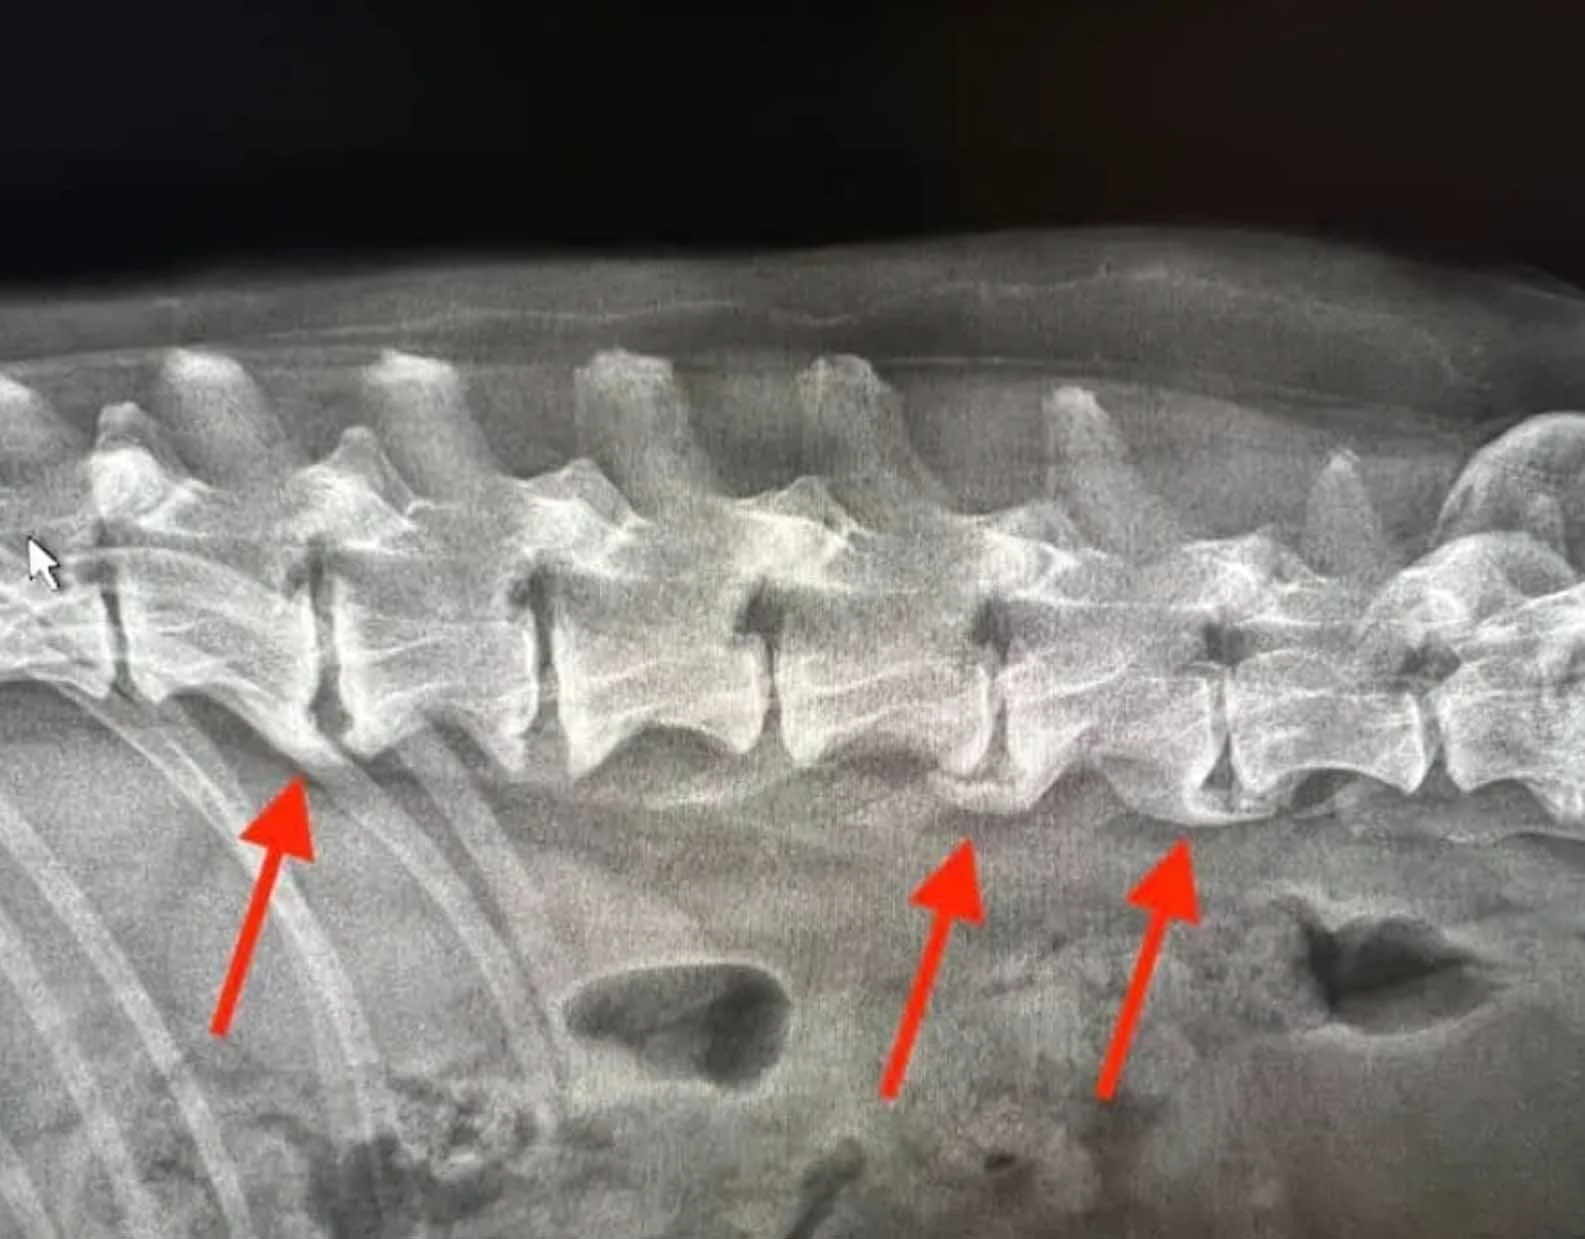

Spondylosis Deformans

Spondylosis deformans is a degenerative condition of the spine where bony spurs form along the edges of the vertebrae. It is commonly associated with ageing and wear on the spinal joints and is frequently seen in large, heavy-boned breeds such as the Cane Corso.

In many cases, spondylosis is an incidental finding and does not cause clinical symptoms. However, in more advanced cases, it can contribute to stiffness, discomfort, or reduced flexibility.